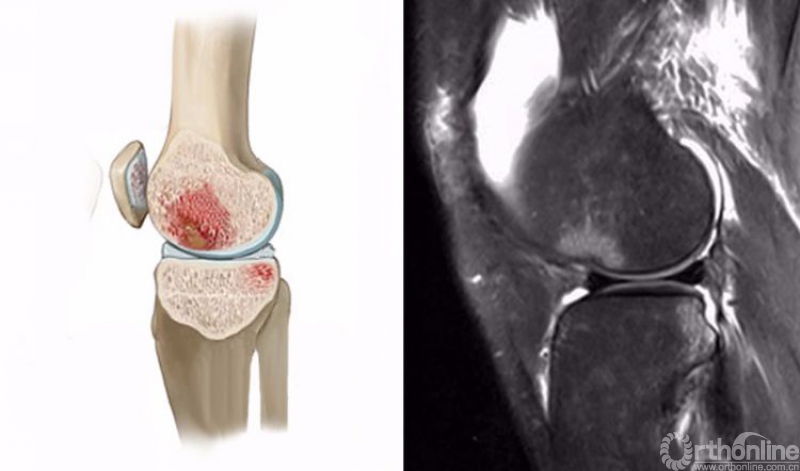

1.轴移损伤(pivot-shift injury)

膝关节在不同程度的屈曲和胫骨外旋或股骨内旋状态下,受到外翻力的作用。通常在快速减速并改变方向的时侯发生前交叉韧带(ACL)撕裂,一旦ACL撕裂,胫骨就相对于股骨前移,使股骨外侧髁和胫骨外后方撞击。其屈曲的程度决定股骨髁挫伤的部位。

膝关节轴移损伤在MRI上主要表现为股骨外侧髁和胫骨外后方骨髓水肿,T2WI及STIR像呈高信号改变,一般预示着ACL损伤。